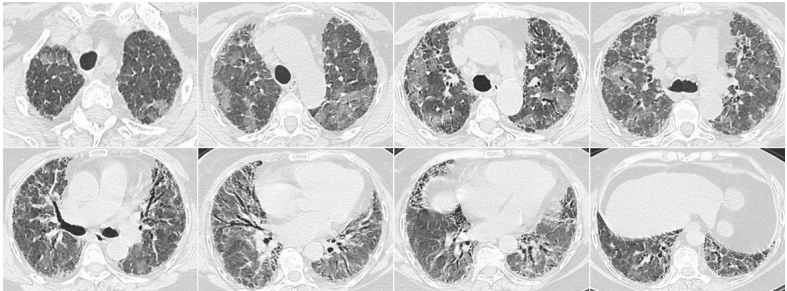

患者,女,50岁;活动后喘息20天,加重伴发热3天,2021年11月19日转入我院。入院胸部CT显示:双肺实变,磨玻璃影(图1)。11月24日复查胸部CT可见病变进展迅速(图2)。予患者气管插管机械通气、俯卧位等,呼吸衰竭未见改善。遂于11月25日启动VV-ECMO(转速2860 rpm,流量4.5 L/min,氧浓度100%)。追问病史:患者入院前1月有活动后气促症状,自觉全身不适,近2年有眼干、口干不适。进一步检查发现,ANA反应阳性(+),ANA核型为胞浆颗粒型(异常);抗SSA/Ro抗体阳性(++)、抗Ro-52抗体阳性(+++)。诊断:急性间质性肺炎(AIP);Ⅰ型呼吸衰竭;混合性结缔组织病。治疗:VV-ECMO+呼吸机辅助通气+俯卧位通气、激素(甲强龙80 mg×7天,60 mg×3天,40 mg qd)、免疫抑制剂(环磷酰胺400 mg qd×3天)、抗感染(哌拉西林他唑巴坦4.5 g q12h+莫西沙星0.4 g qd+氟康唑氯化钠注射液20 mg qd)、抗凝等。在随后的一段时间内,患者影像学改善不明显(图3)。直至12月20日,复查胸部CT可见患者肺部病变较前明显吸收(图4)。2021年12月31日VV-ECMO撤机后,继续气切呼吸机辅助通气,甲强龙40 mg qd抗炎治疗,继续抗感染治疗,2022年1月7日脱机,1月21日气管封管,1月26日出院。后续治疗:强的松25 mg qd,环磷酰胺600 mg q2w×4次,序贯吗替麦考酚酯0.5 g bid。重症间质性肺疾病(ILD)在诊断方面需要考虑以下问题:是ILD吗?是哪种ILD?严重程度如何?在治疗方面,除了生命支持(呼吸支持重点)和病因治疗,并发症的处理也至关重要。重症ILD的诊断包括两方面,一方面是通过影像学、病史+临床表现、BALF-NGS、实验室检查、肺活检等对ILD进行诊断;另一方面涉及重症,患者多面临呼吸衰竭甚至多器官衰竭,因此时间更加紧迫。在ICU内最常见的重症ILD包括:特发性肺纤维化急性加重(AE-IPF)、自身免疫相关性ILD、肿瘤治疗相关性ILD、隐源性机化性肺炎(COP)、AIP、过敏性肺炎(HP)、急性嗜酸性粒细胞性肺炎(AEP)、药物相关ILD等。在影像学方面,最易导致重症的类型有弥漫性磨玻璃影和实变影。最常见的鉴别诊断就是重症肺部感染。表现为弥漫性磨玻璃影或实变影的ILD较为多见,例如:HP、嗜酸性粒细胞性肺炎(EP)、结缔组织病相关间质性肺病(CTD-ILD)、非特异性间质性肺炎(NSIP)、脱屑性间质性肺炎(DIP)、淋巴细胞性间质性肺炎(LIP)、机化性肺炎(OP)、AE-IPF、肺泡蛋白沉积症(PAP)、肺泡微结石症、结节病、弥漫性肺泡出血综合征、肺水肿等。而很多感染性疾病影像学也可表现为磨玻璃影,例如:卡氏肺孢子菌肺炎(PCP)、病毒性肺炎、巨细胞病毒性肺炎、支原体肺炎。尽管如此,ILD也有部分影像学具有特征性,可以被识别。图5左表现为肺陷闭,也称为“猪头肉冻征”,这是典型的亚急性HP的影像学特征。图5右表现为弥漫性磨玻璃影,但以肺门向外扩展,外面有肺大泡,这是典型的PCP表现。临床上多见自身免疫性疾病导致的ILD,此类疾病也具有共同的特征,例如双肺弥漫,病理方面以NSIP或OP为主要特征。但也有部分患者可以出现弥漫性肺泡损伤(DAD)特征。如图6所示,左图为ANCA相关性血管炎,右图为MDA5相关性间质性肺病。因此,一定要警惕容易发生这种病理改变的自身免疫性疾病。